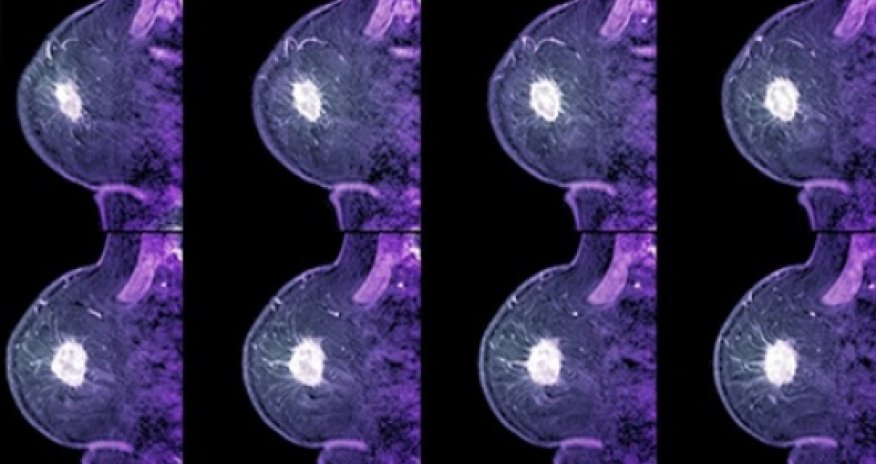

A "landmark study" shows a drug can more than halve the development of breast cancer in high-risk women.A trial on 4,000 women, published in the Lancet, showed anastrozole was more effective, cheaper and had fewer side effects than current medications, BBC reported.It stops the production of the hormone oestrogen, which fuels the growth of the majority of breast cancers.Doctors and campaigners are asking health services to consider offering the drug to healthy women.Some countries already offer the drugs tamoxifen and raloxifene to prevent breast cancer. They both block oestrogen activity, however, they also increase the risk of cancers of the womb, deep vein thrombosis and hot flushes.Aromatase inhibitors, such as anastrozole, stop oestrogen being produced in the first place and are already used as a treatment for breast cancer.'More effective'The study at Queen Mary University of London has followed women with a high risk of breast cancer, based on their family history, for an average of five years.It showed that out of 2,000 high-risk women given no treatment there were 85 cases of breast cancer in the study.But in the same number of women given anastrozole there were 40 cases, with virtually no side-effects.Lead researcher Prof Jack Cuzick, who also pushed for the introduction of tamoxifen, told the BBC: "I think this is an exciting moment, breast cancer is by far the most common cancer in women and we have a chance to reduce cases."He added: "This class of drugs is more effective than previous drugs such as tamoxifen and crucially, it has fewer side effects."Prof Cuzick said there was now enough evidence to consider offering the drug.Prof Montserrat Garcia-Closas, from the Institute of Cancer Research in London, who led the world's largest study into the causes of breast cancer, told the BBC: "This is a very significant and very important finding."The question now is will it reduce mortality and that will require longer term studies."But it adds very important evidence for recommending the drug as an alternative to tamoxifen, we now need to identify those women at highest risk who will benefit the most from this treatment."Post-menopauseBoth tamoxifen and anastrozole are cheap as the patents have run out on the drugs. For five years of treatment, tamoxifen would cost £157 and anastrozole £137.However, anastrozole cannot prevent the ovaries producing oestrogen so it would work only after the menopause. Tamoxifen works both before and after.In 2013, the National Institute for Health and Care Excellence, in England and Wales, said high-risk women, over 35, should be offered tamoxifen or raloxifene.The decision affected around 500,000 women. Cancer Research UK estimates that 240,000 of them would be suitable for anastrozole.Prof Mark Baker, from NICE, commented: "We will certainly consider this research - along with all other available evidence - when the NICE guideline on familial breast cancer is next updated."But he cautioned that tamoxifen was recommended for just a "relatively small percentage" of people so far.Dr Caitlin Palframan, the head of policy at the charity Breakthrough Breast Cancer, commented: "The challenge will be ensuring drugs like these are actually offered on the NHS, as many eligible women still don't have access to the risk-reducing treatments already recommended in national guidelines. "Kate Law, the director of clinical research at Cancer Research UK, which part funded the study, said: "This landmark study shows that anastrozole could be valuable in helping to prevent breast cancer in women at higher-than-average risk of disease."We now need accurate tests that will predict which women will most benefit from anastrozole and those who will have the fewest side-effects."ANN.Az